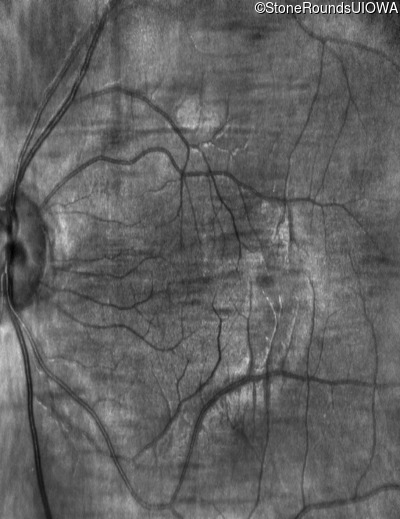

Infrared Fundus Photograph - Right - 10/160 sc

Exemplar

Infrared Fundus Photograph - Left - 10/200 sc